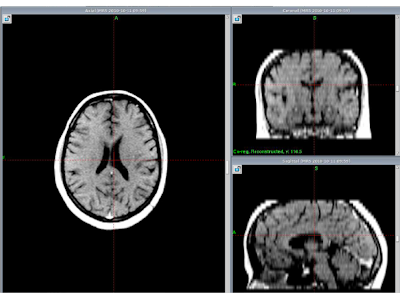

MRI showed

non enhancing mass

periventricular area

more on Lt. side.

Complete resolution after one year of Gamma knife Treatment.

At GKRS                             After one year                              After Two years